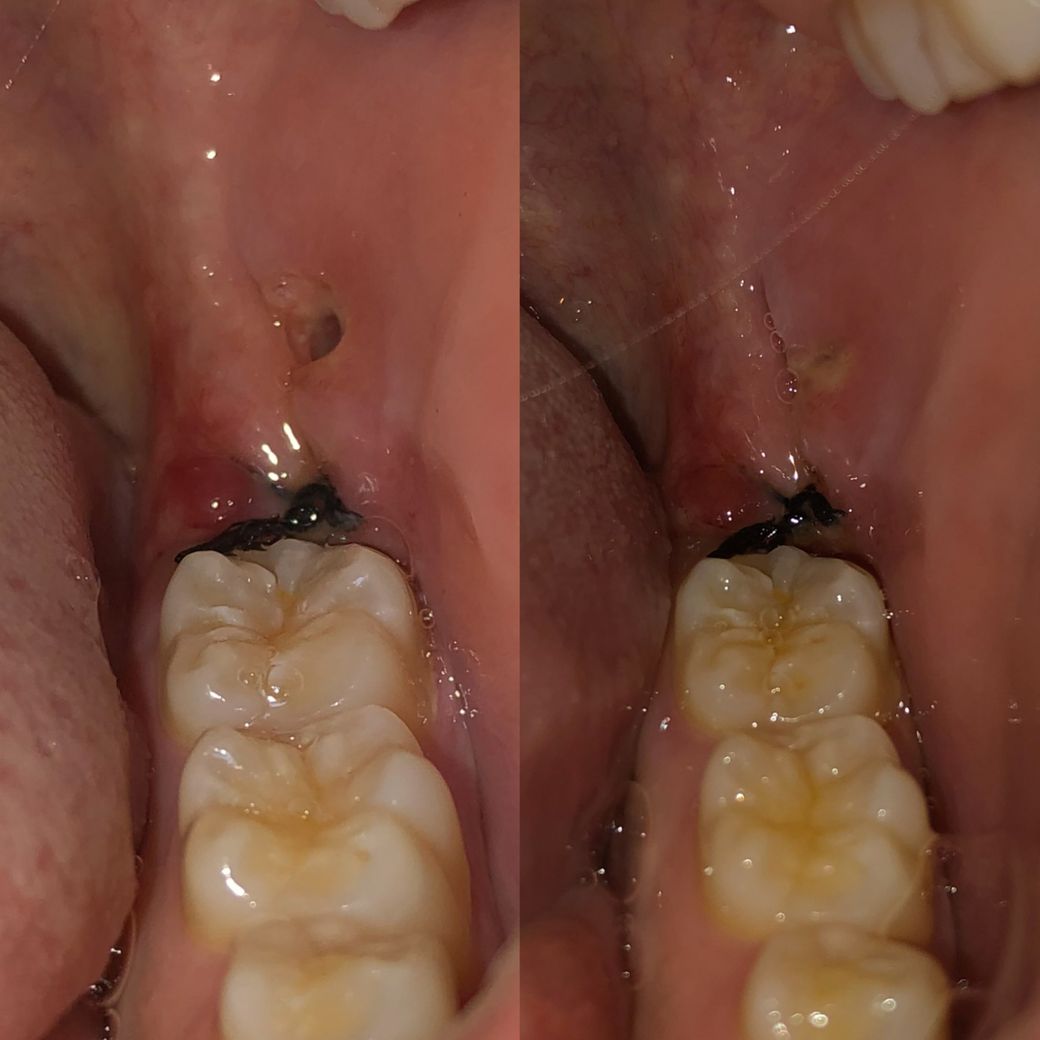

오늘 매복 사랑니를 발치했는데 지혈이 된 후 확인해봤을 때는 구멍이 있었어요 약 12시간이 지난 후 다시 보니까 구멍이 채워져 있는데 이게 육아조직인지 음식물 이물질인지 궁금합니다.....

질문하신 내용에 대하여 아래와 같이 답변 드립니다.사진상에서 보았을 경우 적절히 봉합이 이루어졌으며, 해당 부위로 약간 노랗게 비춰보이는 육아조직이 관찰됩니다.

질문하신 내용에 대하여 아래와 같이 답변 드립니다.왼쪽에 있는 구멍은, 잇몸 절개 후 발치 후 다시 봉합했을 때, 봉합이 되지 않은 빈 곳인것 같습니다.

오른쪽은, 발치 후 잇몸이 붓게되면서, 그 공간이 어느정도 덮힌 것으로 보입니다.